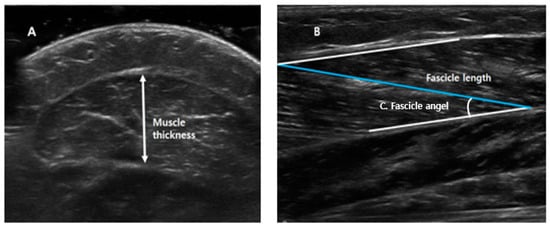

All ultrasound measurements were obtained with the ankle in 10° of plantarflexion, at a neutral angle (0°), and at 10° of dorsiflexion. GCM thickness, fascicle length, and fascicle angle were measured as shown in Figure 1. Muscle thickness (Figure 1A) was defined as the longest distance between fascia of GCM in the cross-sectional area; the fascicle length (Figure 1B) was calculated as the linear distance between the insertion of a fascicle into the lower and upper aponeuroses; and fascicle angle (Figure 1C) was defined as the angle between muscle fiber and estimated parallel fascia line.

Figure 1. Measurements of medial head of the gastrocnemius muscle thickness, fascicle length, and fascicle angle. (A) Muscle thickness: the longest distance between fascia of gastrocnemius muscle in cross-sectional area. (B) Fascicle length: the linear distance between the insertion of a fascicle into the lower and upper aponeuroses. (C) Fascicle angle: the angle between muscle fiber and estimated parallel fascia line.